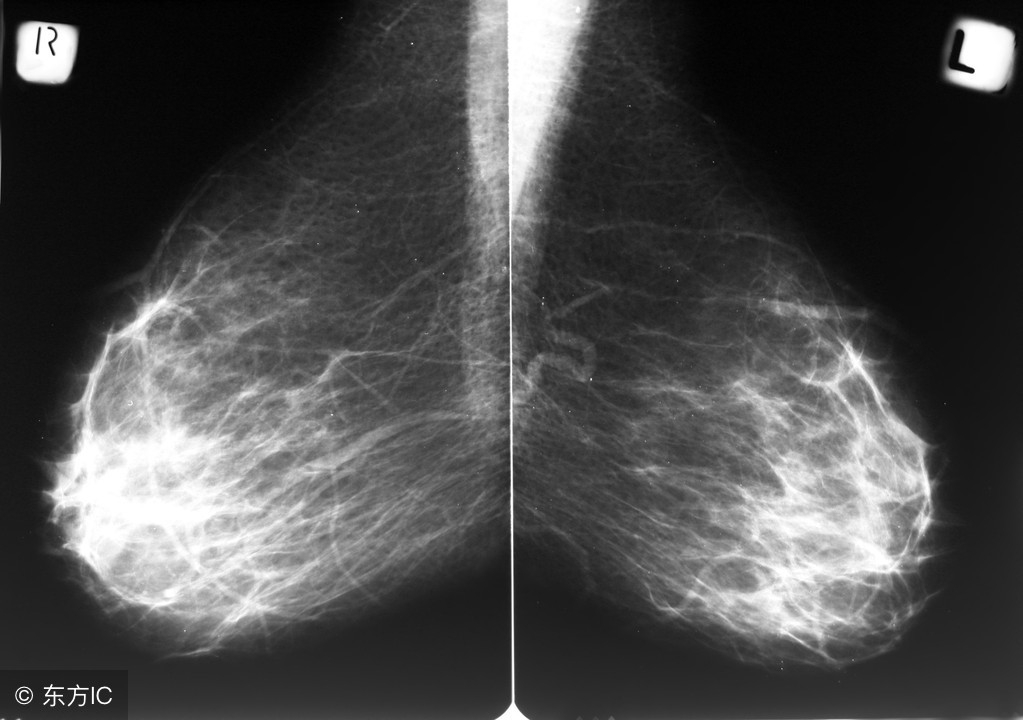

乳腺增生是最常见的一种良性乳腺疾病,乳腺在正常的发育和退化过程中,增生和复旧节律失常导致的一种乳腺良性疾病,主要是表现为乳腺正常结构不同程度的紊乱。

增生的本质就是乳腺正常结构不同程度的紊乱